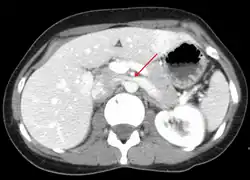

Compression of the left renal vein (marked by the arrow) between the superior mesenteric artery (above) and the aorta (below) due to nutcracker syndrome.

| The nutcracker syndrome results from compression of the left renal vein between the aorta and the superior mesenteric artery. | |